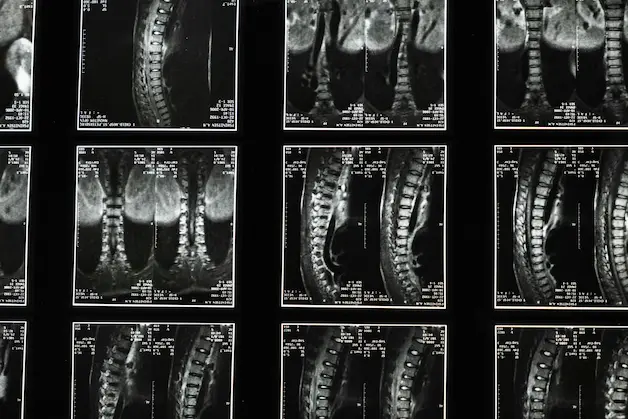

Spinal decompression is a non-surgical treatment option that aims to relieve pressure on the spinal discs and surrounding structures. This blog explores various aspects of spinal decompression, including techniques, safety, and treatment options.

Spinal decompression treatment is a therapeutic approach that can alleviate symptoms associated with conditions like herniated discs and sciatica. Treatment plans often include a combination of therapies, such as physical therapy, chiropractic care, and sometimes medication, to enhance recovery.